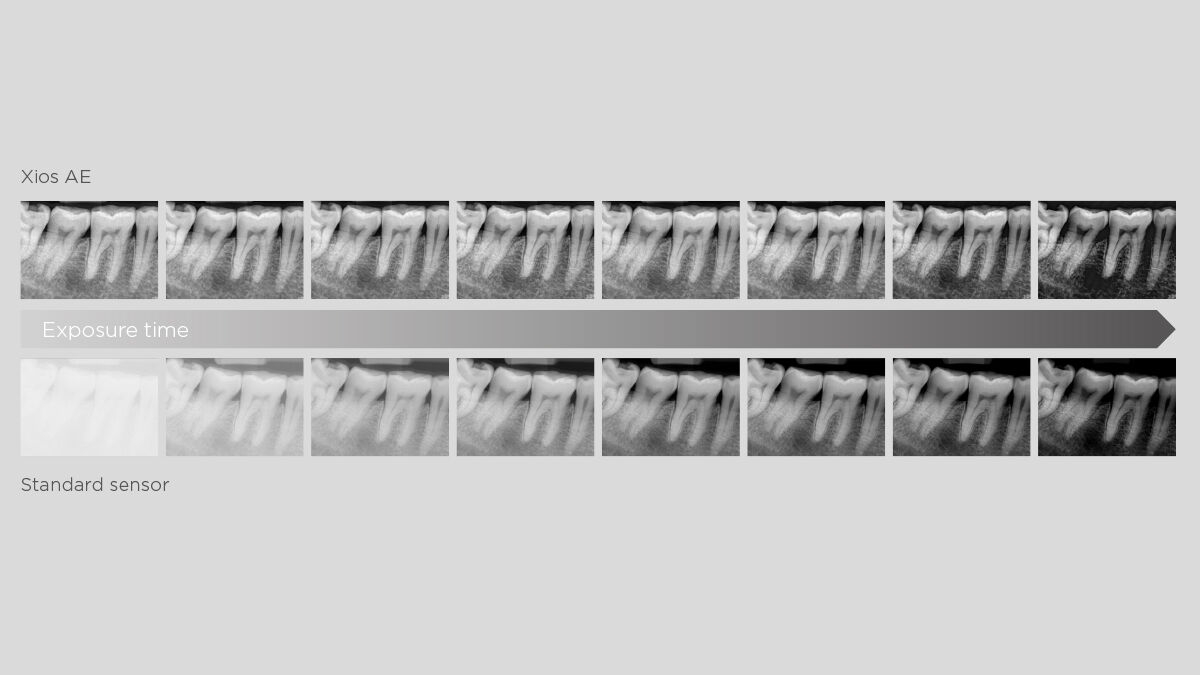

Increased sensor sensitivity and an enhanced low-dose optimized exposure spectrum allow for optimal visibility and diagnostics at reduced exposure. Underexposed images are successfully counterbalanced, granting consistent image quality and dose flexibility.

Xios AE Sensor

Xios AE - Gallery of sample images